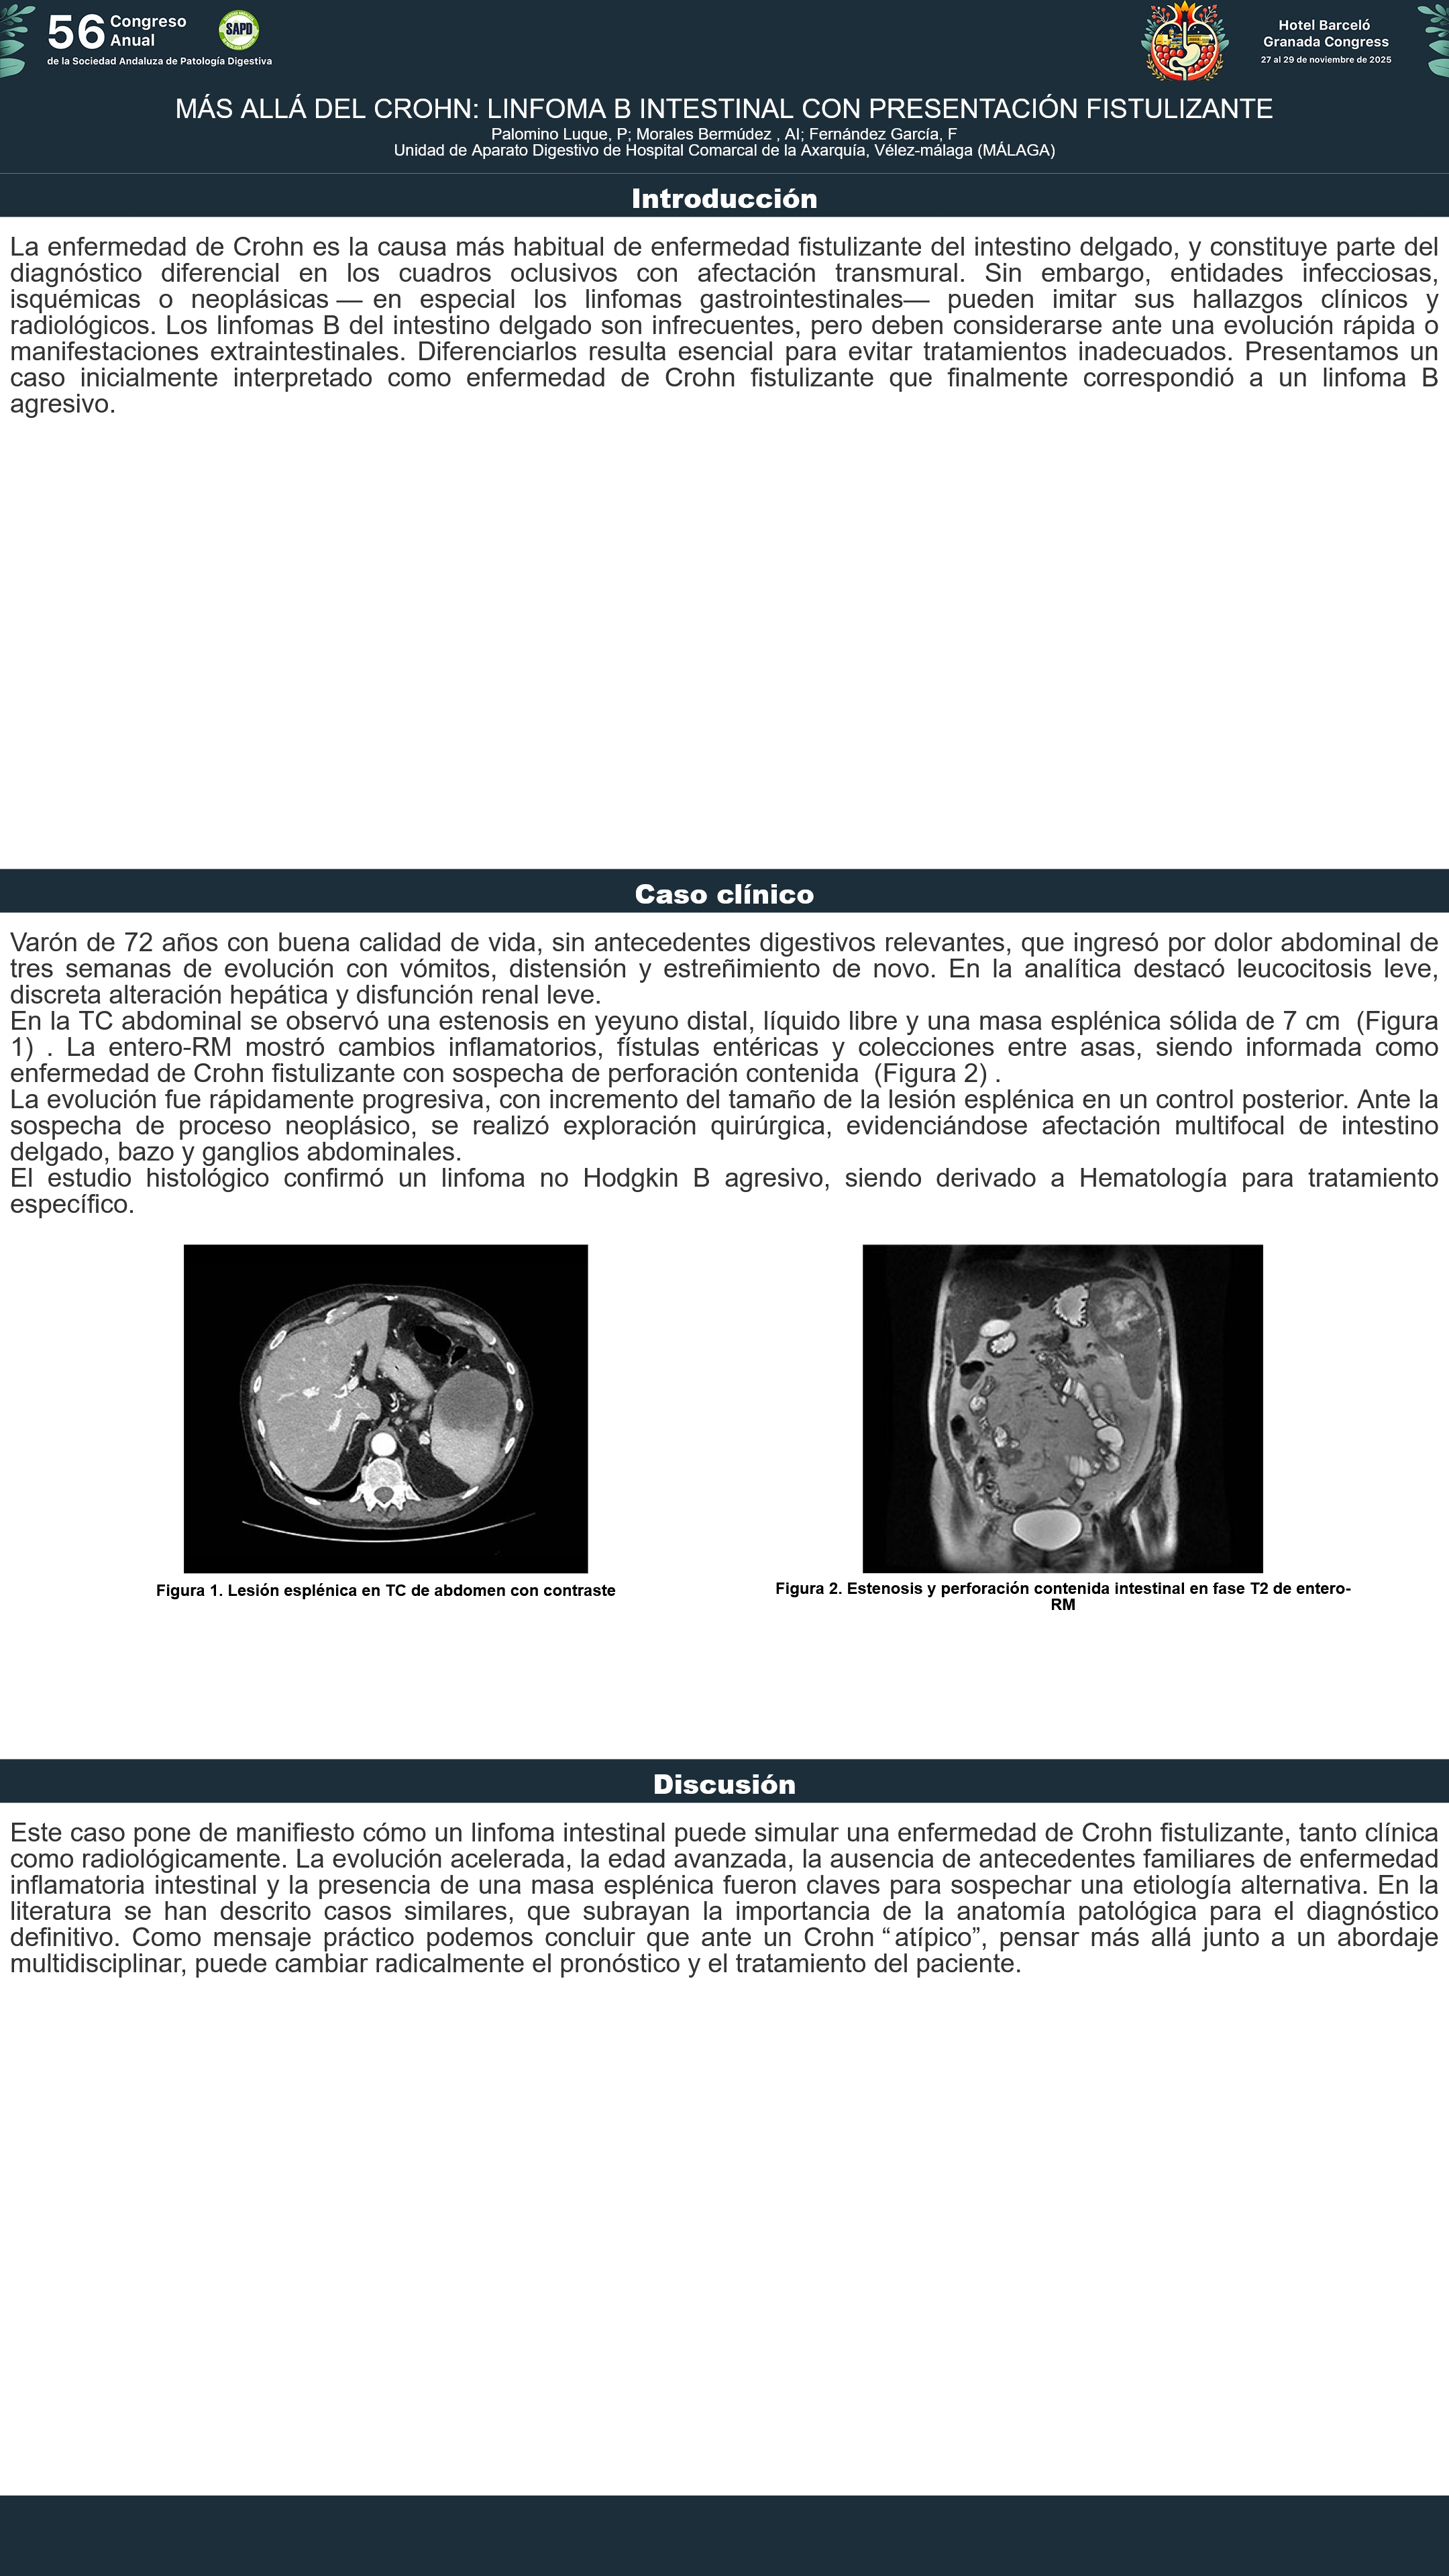

[CP-105] MÁS ALLÁ DEL CROHN: LINFOMA B INTESTINAL CON PRESENTACIÓN FISTULIZANTE